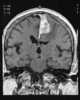

Intracerebral abscess